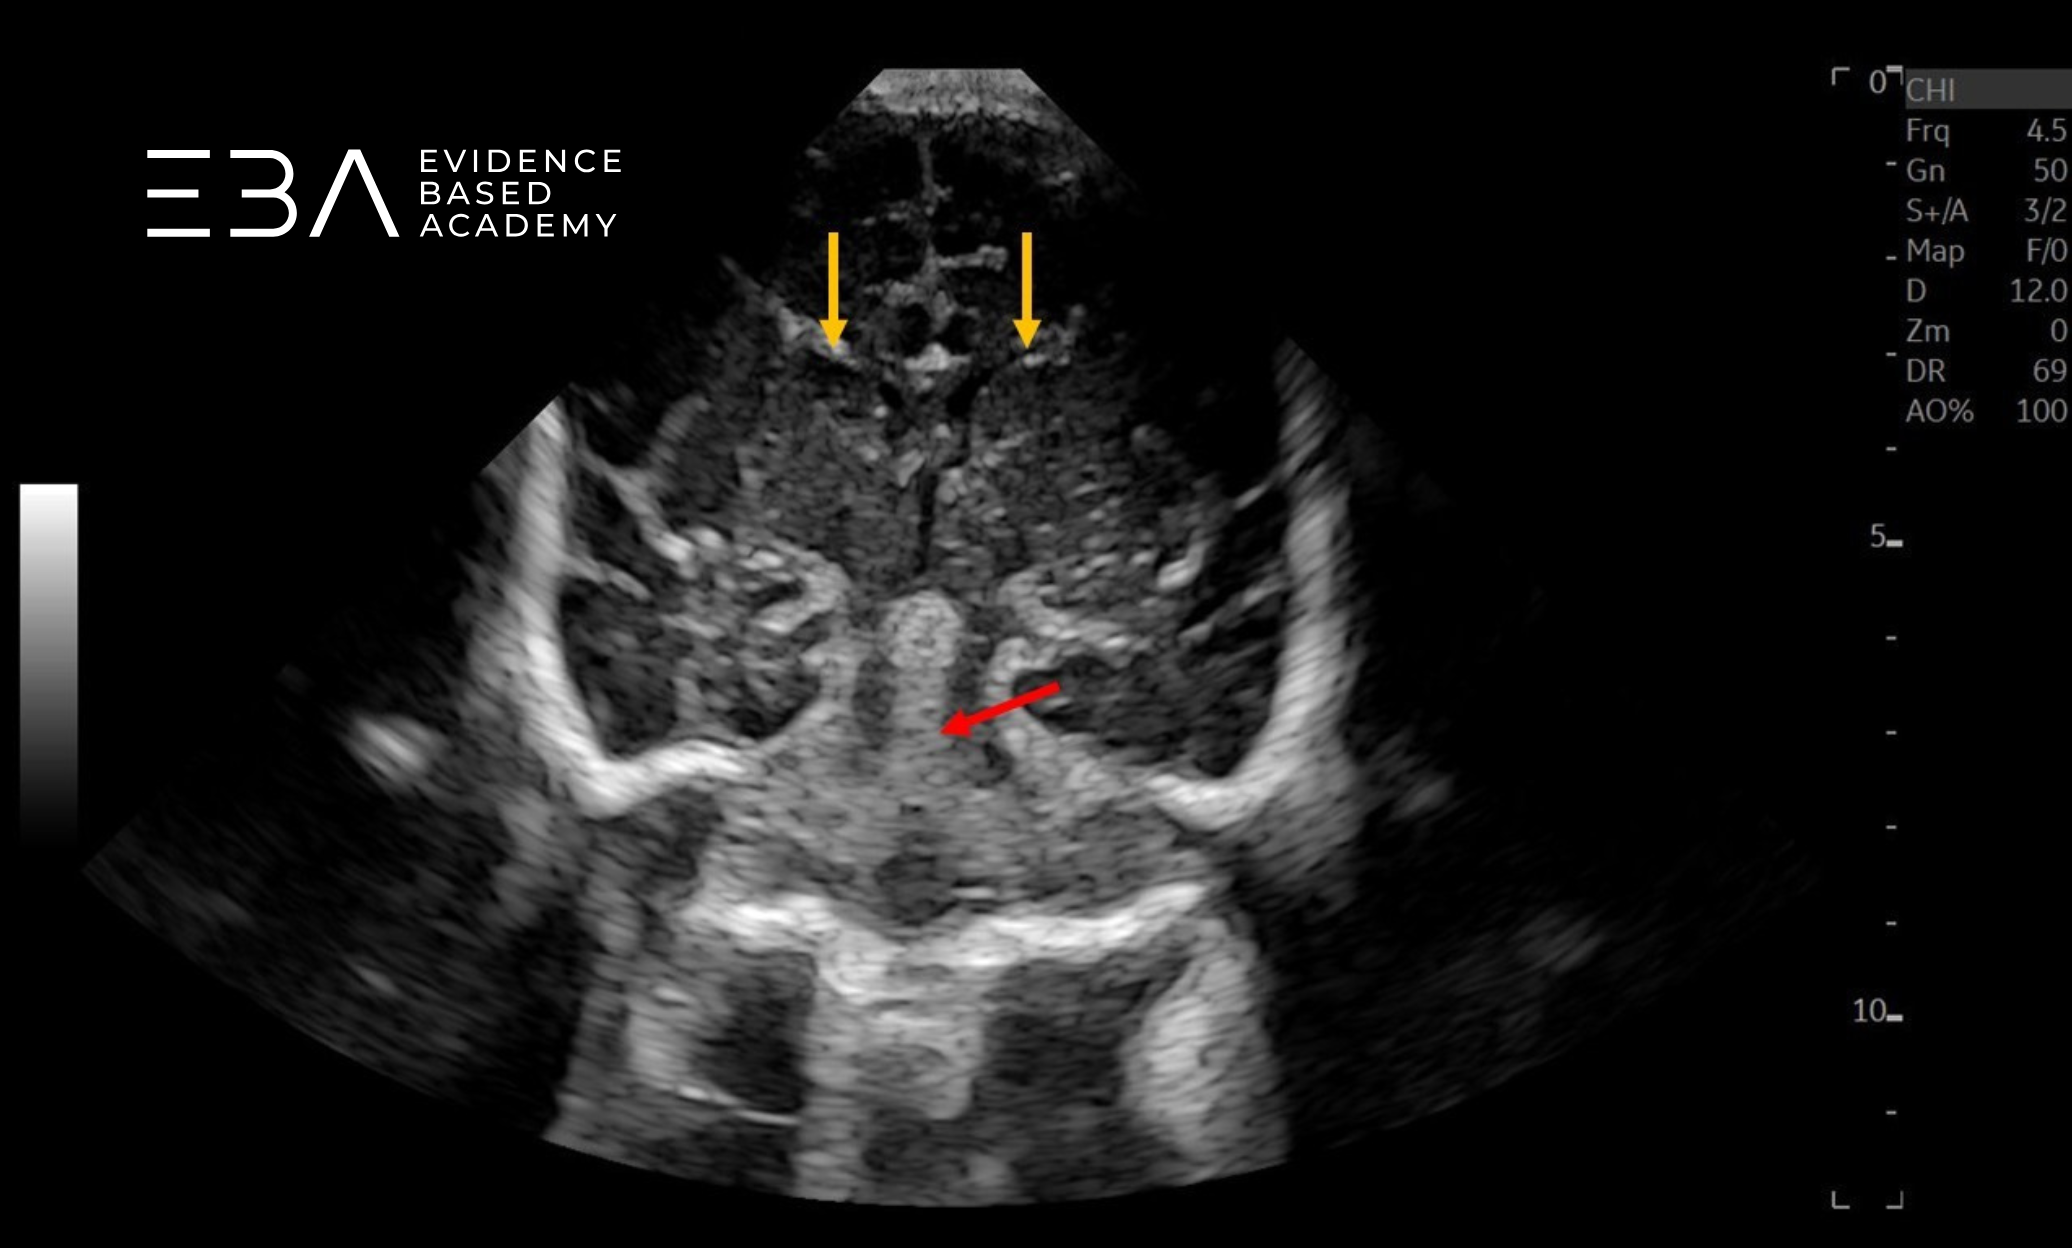

zdj. 5a

Głowica liniowa – badanie przez łuskę kości skroniowej. Konary mózgu (żółte strzałki), wodociąg mózgu (czerwona strzałka).